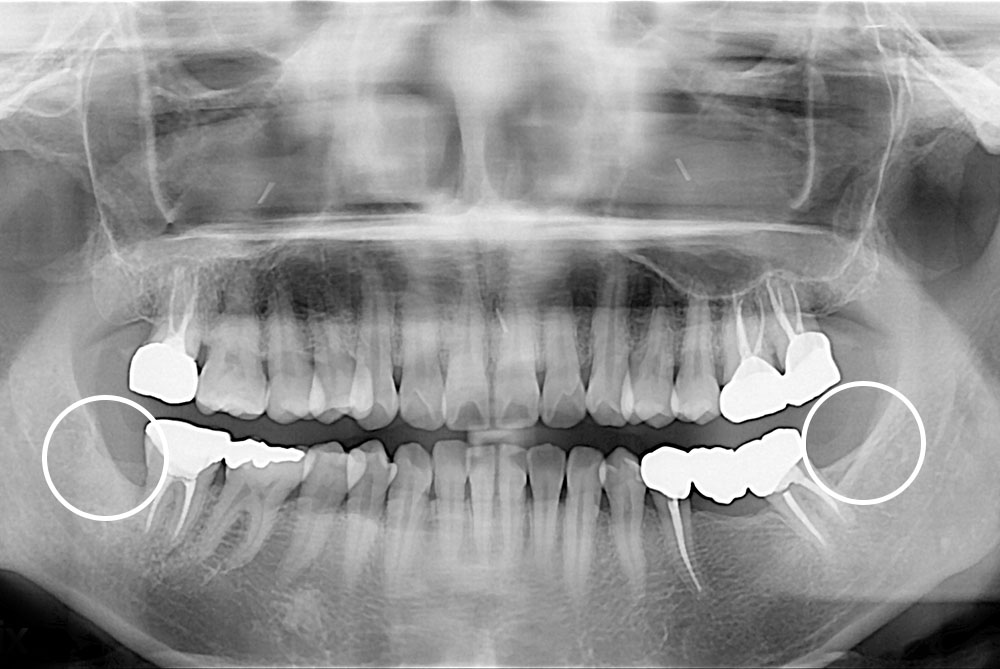

[사랑니] 매복 사랑니 발치

치료전 : 2017-12-01